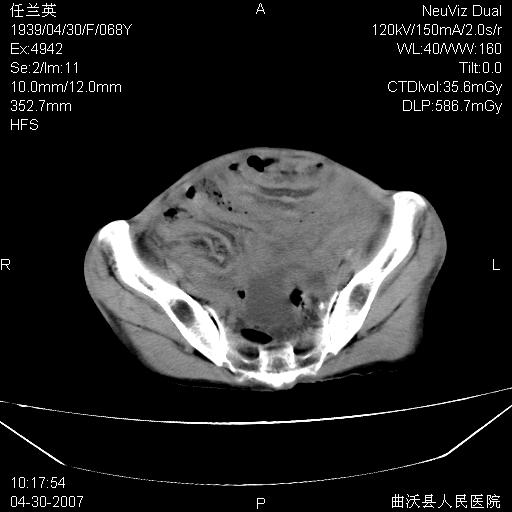

患者,女,68岁,感觉腹部憋涨发硬数天,查b超发现左盆腔有囊性肿物和少量腹水,行ct检查

支持左侧卵巢恶性肿瘤伴网膜、腹膜广泛转移。

支持:左侧卵巢恶性肿瘤伴网膜、腹膜 腹膜后(淋巴结)广泛转移。

网膜、腹膜广泛转移考虑来源于左侧卵巢癌可能性大。不除外来源于消化系的肿瘤。